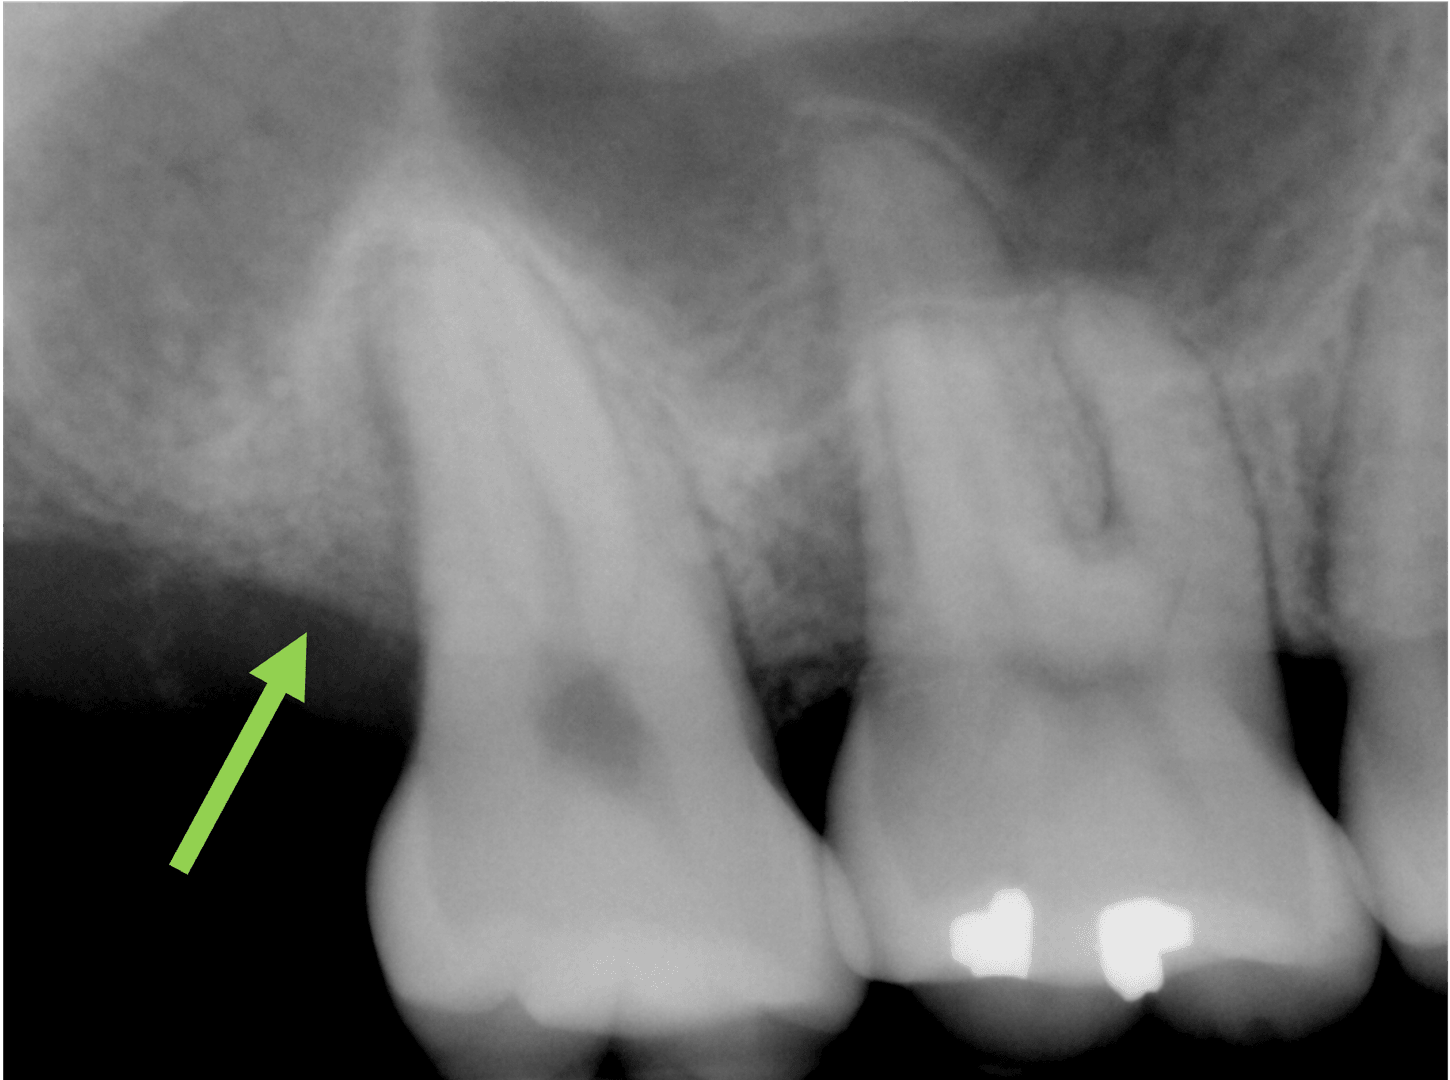

치주 재생 수술을 통한

치조골의 재생

치주 재생 수술을 이용한

치조골의 재생을 확인할 수 있습니다

치료 후

본 이미지는 촬영 조건에 따라 실물과 일부 다르게 보일 수 있으며, 환자 본인의 동의를 얻어 촬영 후 게재하였습니다.

치료 결과는 환자 개개인의 상태에 따라 다르며, 치과의사의 상담이 필요합니다.